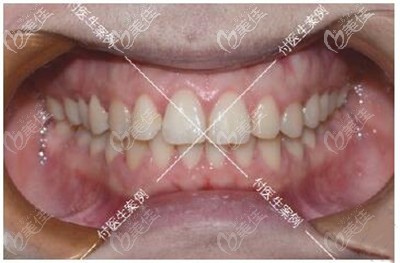

術(shù)后照片:

深覆合牙齒矯正前后牙齒效果對比

我做牙齒矯正一共花了差不多500多天,看我矯正后的效果,牙齒咬合調(diào)整好了,之前反頜的牙齒也歸隊了,重點是沒想要深覆合做牙齒矯正真的會對臉型有影響!

我現(xiàn)在下巴出來了,笑起來更舒展了,再也不怕會露牙齦了。身邊的朋友多懷疑我去做了整形,問我是不是悄咪咪的墊下巴了!哈哈,反正這個矯正效果我真的很滿意,現(xiàn)在的側(cè)面弧度我真的愛了。